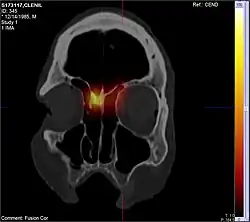

| Diagnostic method | Looking up the nose, CT scan[1] |

The exact cause is unclear.[1] They may be related to chronic inflammation of the lining of the sinuses.[1] They occur more commonly among people who have allergies, cystic fibrosis, aspirin sensitivity, or certain infections.[1] The polyp itself represents an overgrowth of the mucous membranes.[1] Diagnosis may be accomplished by looking up the nose.[1] A CT scan may be used to determine the number of polyps and help plan surgery.[1]

CT scan

CT scan can show the full extent of the polyp, which may not be fully appreciated with physical examination alone. Imaging is also required for planning surgical treatment.[7] On a CT scan, a nasal polyp generally has an attenuation of 10–18 Hounsfield units, which is similar to that of mucus. Nasal polyps may have calcification.[14]